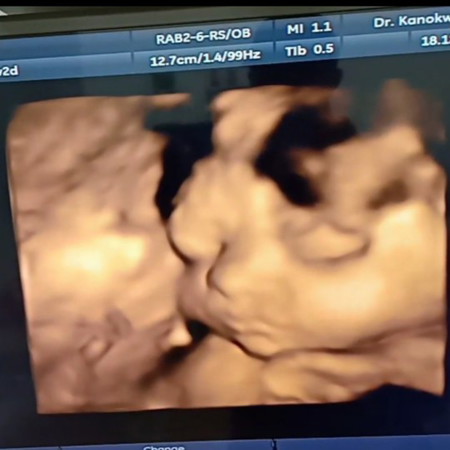

ซาวด์ตอน 36w ตอนนี้ 37w แล้วค่ะ เพศชาย หนัก 2900กรัม แก้มก็จะยุ้ยๆหน่อยน้าาา